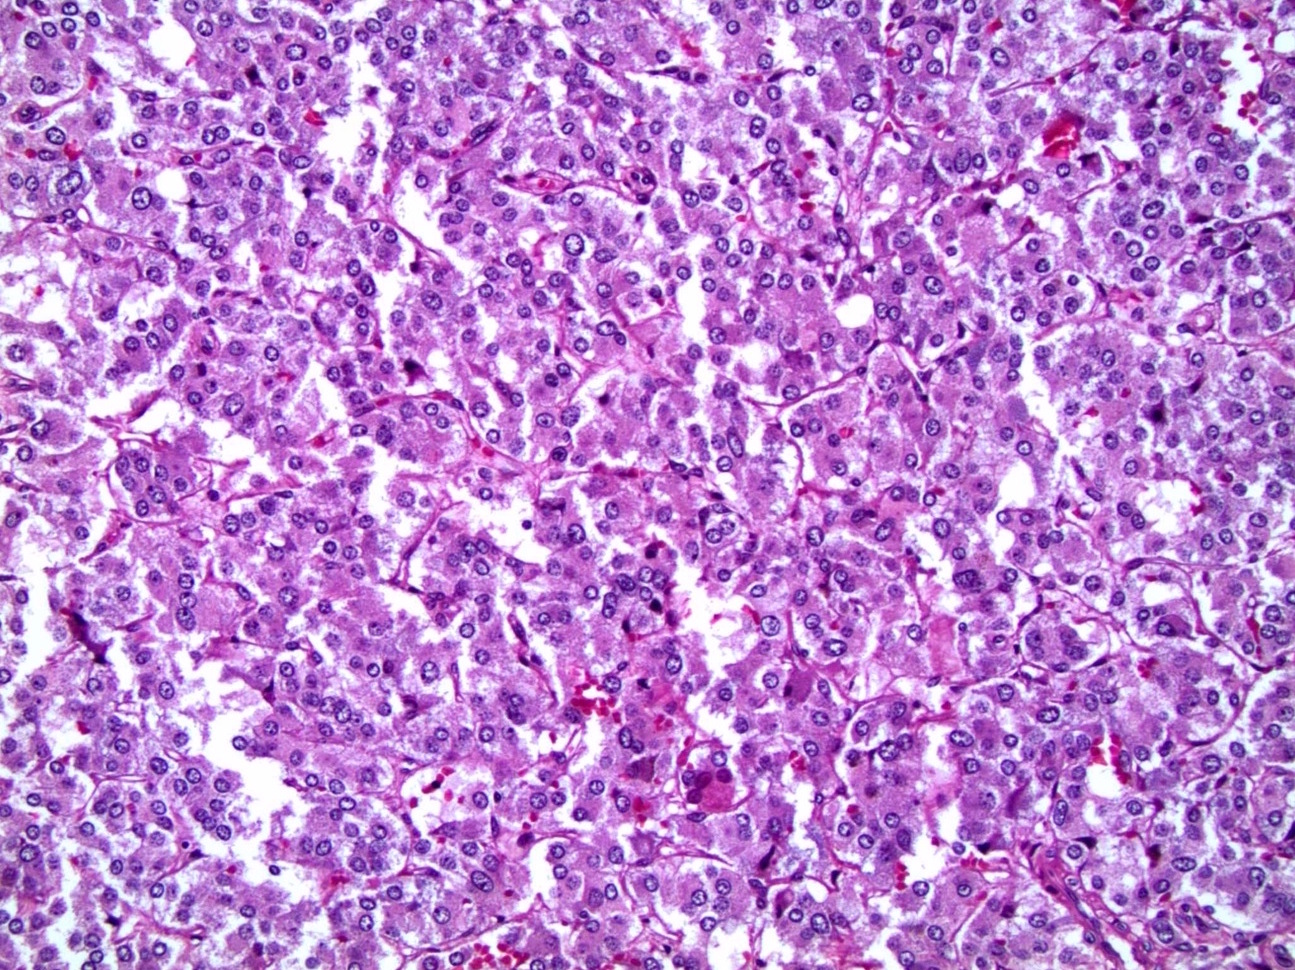

Microscopic (histologic) description

- Nested (zellballen), trabecular or solid arrangement

- Nests outlined with sustentacular cells best visualized with S100 immunostain

- Cells: large, polygonal, uniform or extensively vacuolated

- Cytoplasm: abundant fine, granular red-purple cytoplasm

- Pigmented granules containing hemosiderin, melanin, neuromelanin and lipofuscin may be seen

- Nuclei: may be uniform or exhibit extensive variation in size, round to oval nuclei, nucleoli prominent

Microscopic (histologic) images